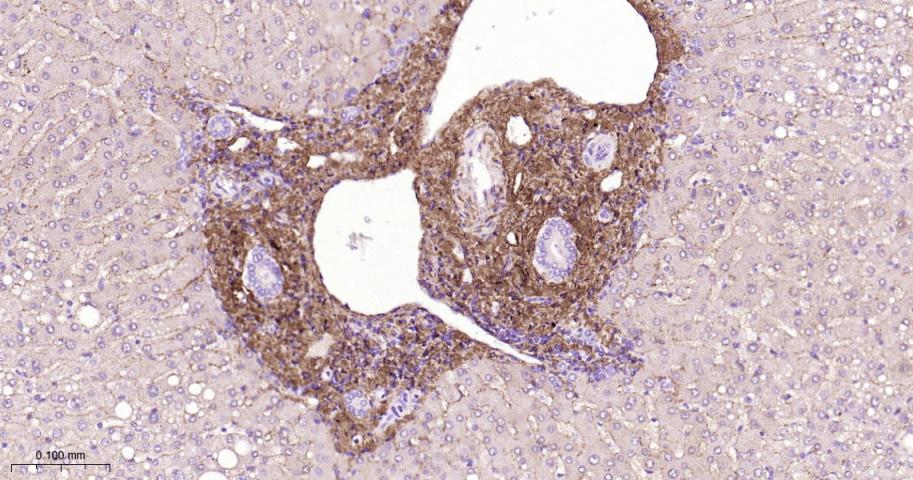

Paraformaldehyde-fixed, paraffin embedded Human Liver; Antigen retrieval by boiling in sodium citrate buffer (pH6.0) for 15 min; The section was incubated with Collagen I Polyclonal Antibody, Unconjugated (bs-10423R) at 1:800 overnight at 4°C, followed by conjugation to the bs-0295G-HRP and DAB (C-0010) staining.

Paraformaldehyde-fixed, paraffin embedded Mouse Liver; Antigen retrieval by boiling in sodium citrate buffer (pH6.0) for 15 min; The section was incubated with Collagen I Polyclonal Antibody, Unconjugated (bs-10423R) at 1:800 overnight at 4°C, followed by conjugation to the bs-0295G-HRP and DAB (C-0010) staining.